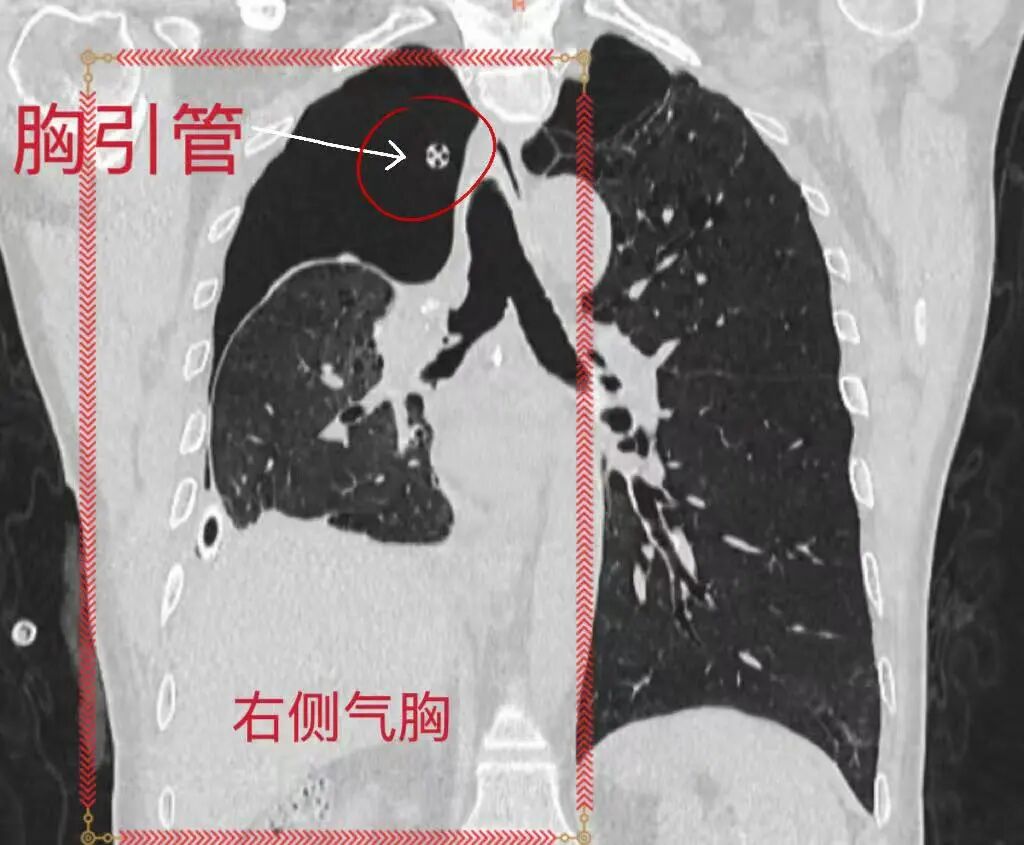

近日,重庆医科大学附属璧山医院(重庆市璧山区人民医院)呼吸与危重症医学科气道介入团队再获诊疗新突破,成功为患者精准定位复杂支气管胸膜瘘(Bronchopleural Fistula, BPF)瘘口,并实施微创堵瘘治疗,帮助其顺利拔除胸腔引流管,康复出院。

【厚德精医】精准定位复杂瘘口,微创封堵破解难题